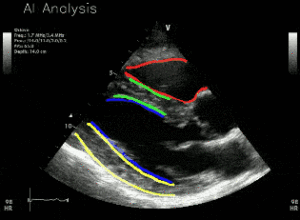

RSIP Vision introduces an innovative set of AI modules for enhanced medical ultrasound applications. These innovative modules empower a wide range of medical applications by overcoming the main ultrasound challenges – user-dependent acquisition and noisy, clinically challenging images. This improves the workflow and diagnostic accuracy while reducing the overall procedure time. SILICON VALLEY, Calif., June 22, 2020 — RSIP Vision, a global leader in artificial intelligence (AI) and computer vision technology, announced today a new set of AI-based medical ultrasound modules. These advanced modules will serve as AI-based building blocks

Fully automatic